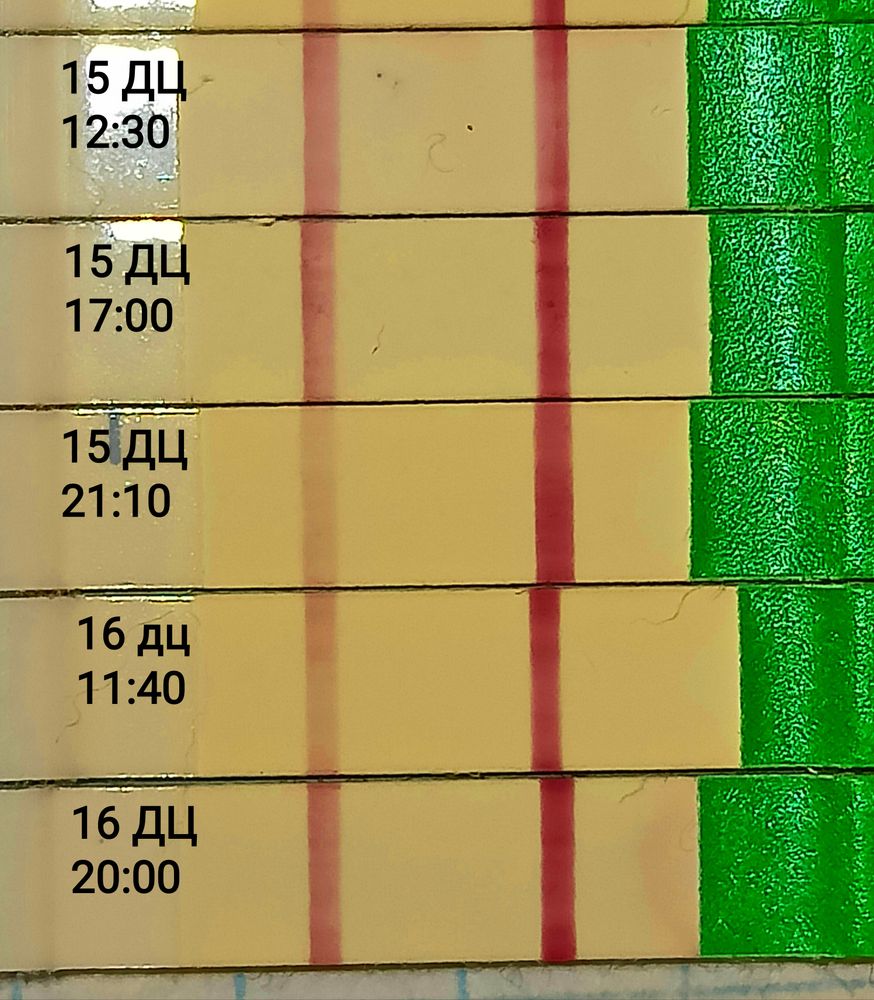

Продолжение...16 ДЦ

Тест снова ярчает вечером сегодня, значит вчера я пик всë таки не пропускала, его просто не было ещё.

Ещё один перед сном замочила и он снова бледнее:

Зачем замочила, до завтра не могла я что ли дотерпеть, сколько тестов уже извела. Достало уже.

Ну , хватит уже тупить на одном месте , то ярче то бледнее .